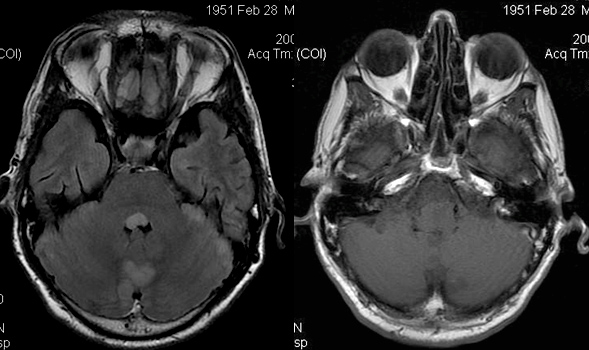

Clinique :

Homme âgé de 48 ans. Lésion révélée par une paralysie faciale progressive avec surdité.

Imagerie IRM :

Large lésion développée dans l’angle ponto-cérébelleux gauche. Très discrète extension visible au niveau du porus intracanalaire. Persistance de la visibilité du LCS au fond du MAI. Lésion hétérogène en iso- et hypersignal T2. Très important rehaussement périphérique à centre hypointense « nécrotique » en T1 après injection de gadolinium.